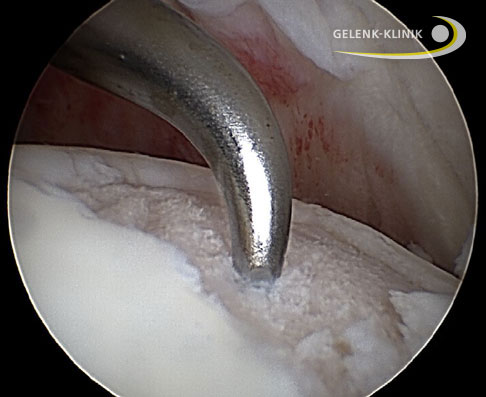

Die Schulterarthroskopie behandelt nicht die Ursache, reduziert aber die Schulterschmerzen und verbessert die Schulterfunktion. Im Rahmen der Arthroskopie entfernt der Schulterspezialist freie Gelenkkörper und entzündete Schleimbeutel (Bursitis). Zeitgleich kann er den Gelenkknorpel glätten, die Gelenkkapsel lockern und die eventuell geschädigte Bizepssehne behandeln.

Der Operateur entfernt störende Osteophyten und kann bei Bedarf eine Neurolyse durchführen, um Schmerzen und Funktionsausfälle aufgrund einer Nervenenge zu beseitigen. Dieses arthroskopische Vorgehen mit der Summe aller genannten Einzelschritte wird auch als CAM-Prozedur (Comprehensive Arthroscopic Management) bezeichnet.

Mikrofrakturierung: Anbohren des Knochens

In manchen Fällen liegt ein kleiner, definierter Knorpeldefekt im Schultergelenk vor. Bei solchen fokalen Defekten kann die Mikrofrakturierung die Knorpelfläche wieder schließen. Durch gezieltes Anbohren des unter dem Defekt liegenden Knochens wird bei der Mikrofrakturierung eine Einblutung in die defekte Stelle ausgelöst. Durch die Heilungsreaktion entsteht an dieser Stelle knorpelähnliches Narbengewebe. Dieser Faserknorpel ist allerdings weniger elastisch und haltbar wie natürlicher Knorpel.